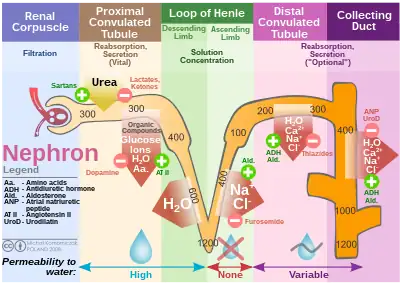

Absorption

The proximal tubule efficiently regulates the pH of the filtrate by secreting hydrogen ions (acid) into the tubule and reabsorbing approximately 80% of the filtered bicarbonate.[6]

Fluid in the filtrate entering the proximal convoluted tubule is reabsorbed into the peritubular capillaries. This is driven by sodium transport from the lumen into the blood by the Na+/K+-ATPase in the basolateral membrane of the epithelial cells.[6]

Sodium reabsorption is primarily driven by this P-type ATPase – 60–70% of the filtered sodium load is reabsorbed in the proximal tubule through active transport, solvent drag, and paracellular electrodiffusion. Active transport is mainly through the sodium/hydrogen antiporter NHE3.[6][7] Paracellular transport increases transport efficiency, as determined by oxygen consumed per unit of Na+ reabsorbed, thus playing a part in maintaining renal oxygen homeostasis.[8]

| water | approximately two-thirds | Mass movement of water and occurs both through the cells and between them,[9] passively via aquaporins (transcellular transport) and between cells through tight junctions (paracellular). |

| sodium | approximately two-thirds | Mass movement of sodium occurs through the cells, by secondary active transport on the apical membrane, followed by active resorption across the basolateral membrane via the Na+/K+-ATPase.[10] The solutes are absorbed isotonically, in that the osmotic potential of the fluid leaving the proximal tubule is the same as that of the initial glomerular filtrate. |

| organic solutes (primarily glucose and amino acids) | 100% | Glucose, amino acids, inorganic phosphate, and some other solutes are resorbed via secondary active transport through co-transporters driven by the sodium gradient out of the nephron. |

| potassium | approximately 65% | Most of the filtered potassium is resorbed by two paracellular mechanisms – solvent drag and simple diffusion.[11] |

| urea | approximately 50% | Paracellular fluid reabsorption sweeps some urea with it via solvent drag. As water leaves the lumen, the concentration of urea increases, which facilitates diffusion in the late proximal tubule.[11] |

| phosphate | approximately 80% | Parathyroid hormone reduces reabsorption of phosphate in the proximal tubules, but, because it also enhances the uptake of phosphate from the intestine and bones into the blood, the responses to PTH cancel each other out, and the serum concentration of phosphate remains approximately the same. |

| citrate | 70%–90%[12] | Acidosis increases absorption. Alkalosis decreases absorption. |

Secretion

Renal corpuscle Diagram outlining movement of ions in nephron.

Diagram outlining movement of ions in nephron.